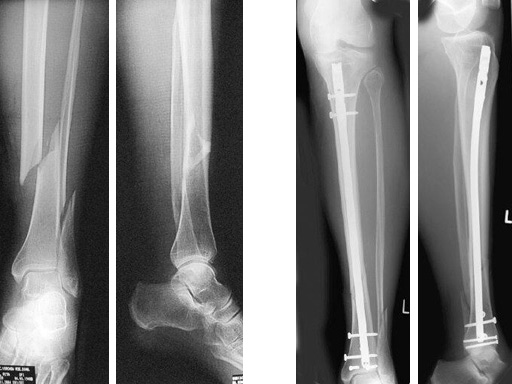

64-year-old woman with an open distal tibial fracture extending into the pilon treated with ETNS.

Type III open distal tibial fracture with beginning compartment syndrom following a traffic accident.